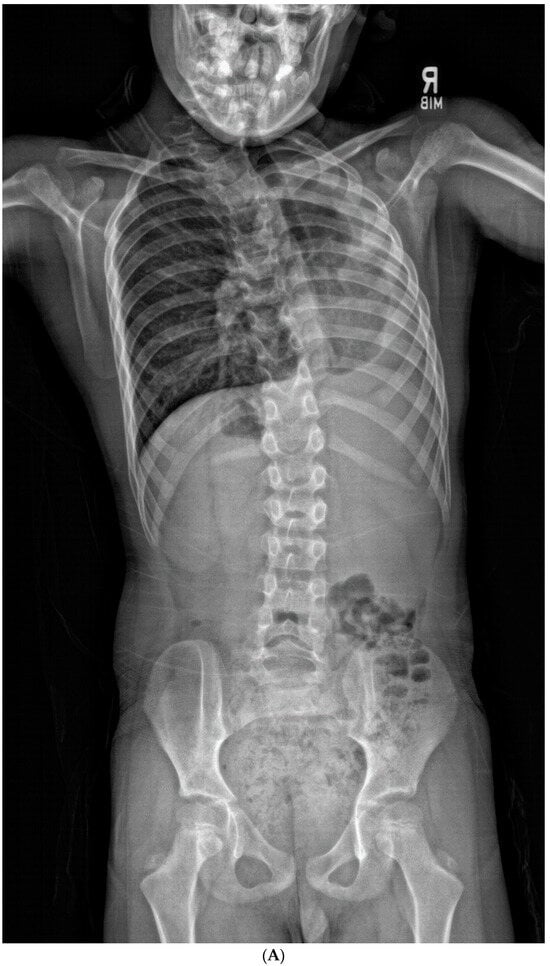

Patients in the “progression” cohort presented with a significantly larger T1S compared to the “no progression” cohort (32.4° ± 14.0° vs. 23.8 ± 7.1°, respectively; p = 0.041, effect size = 0.78). Individual patients with T1S ≥ 25° were found to be 4.62 times more likely to undergo progression than those who did not (Figure 5A–D and Figure 6A–D). Although these findings mostly trended toward significance, patients in the “progression” cohort also had lower C2-SVA (20.8° ± 30.7° vs. 57.5° ± 41.1°, p = 0.053), small thoracic curves (33.2° ± 20.6° vs. 54.1° ± 22.6°, p = 0.063), greater LL (59.3° ± 13.2° vs. 45.3° ± 12.1°, p = 0.056), and smaller interval change in C2-CSVL (−4.9° ± 21.8° vs. 18.4° ± 23.1°, p = 0.069).

Figure 5.

(A,B) Initial PA and lateral radiograph of a 7-year-old child with a 19° cervicothoracic scoliosis and T1 slope of 31°. (C,D) Follow-up PA and lateral radiographs showing progression of the curve to 38° over 8 years.